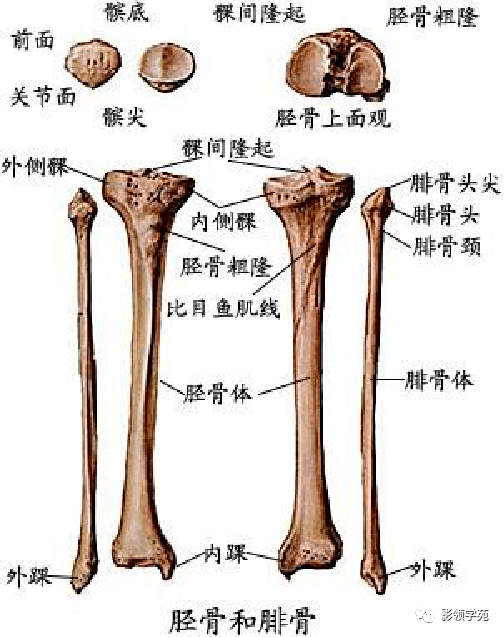

骨骼系统

骨骼系统